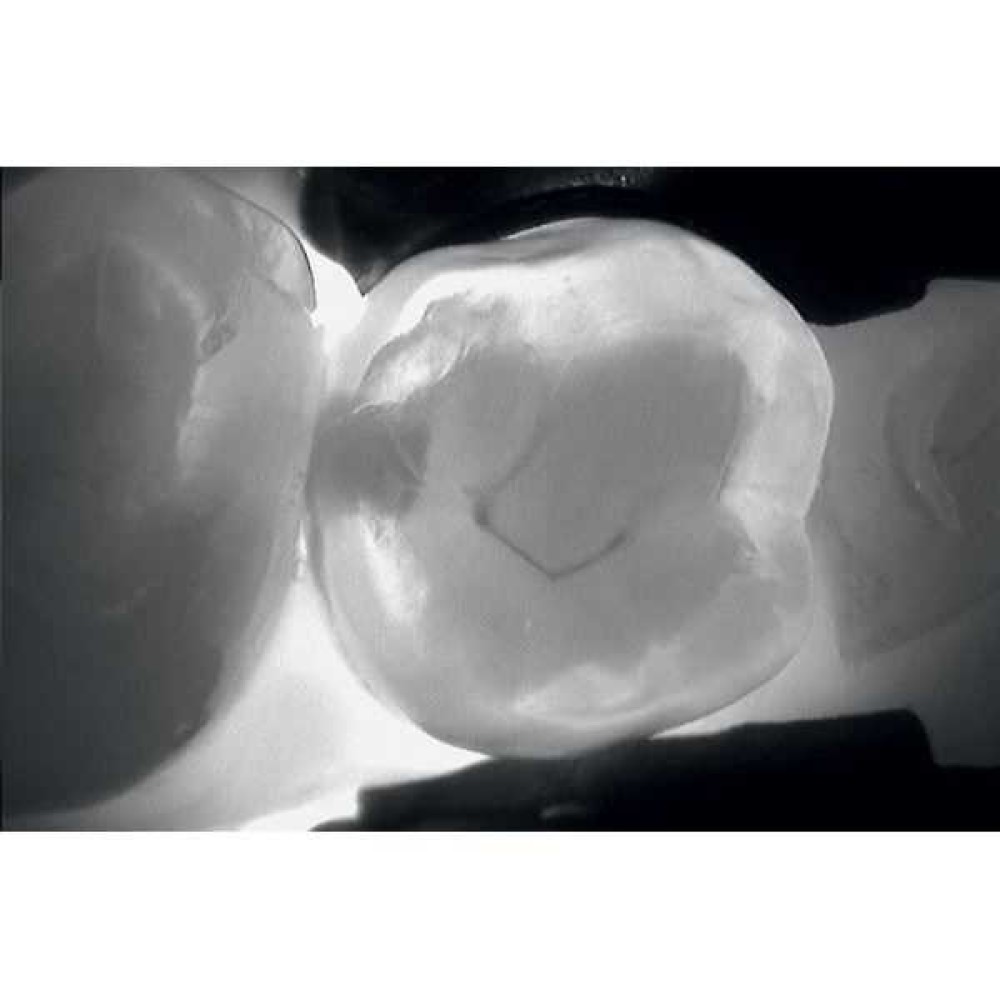

KaVo DIAGNOcam позволяет визуализировать их на аппроксимальных и окклюзионных поверхностях зубов и обеспечивает проведение диагностики вторичного кариеса (при небольшом размере пломбы).

Весь секрет заключается в технологии DIFOTI за счет генерируемого прибором трансилюминационного (трансиллюминация - яркое сквозное освещение) лазерного излучения в нерентгеновском диапазоне волн. Если объяснять это простым языком, то это излучение, занимающее диапазон между видимым светом и рентгеновским диапазоном, которое проходит сквозь твердые ткани зуба, при этом области, не пропускающие свет (например, области кариозного поражения) отображаются в виде затемненных на общем фоне участков.

Цифровая видеокамера фиксирует результат и передает изображение на экран в режиме реального времени.

Рентгенограммы и снимки, полученные с помощью KaVo DIAGNOcam, относятся к методам диагностики, прекрасно дополняющим друг друга. С помощью рентгенологической диагностики Вы в дальнейшем сможете беспрепятственно проверить и дополнить данные KaVo DIAGNOcam, исключив часть рентгеновского излучения для пациента. На снимках отчетливо визуализируются структуры коронковой части зуба, располагающиеся выше уровня десневого края. Таким образом, становится возможным раннее распознавание кариеса и проведение профилактического, малоинвазивного лечения. Ваши пациенты будут в восторге!

- Выявление трещин эмали без применения стоматологического микроскопа.